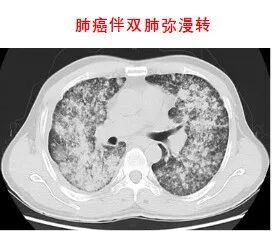

放射治療是利用高能放射線消滅腫瘤的原發灶或轉移灶的一種局部治療方法。是治療惡性腫瘤的三大手段之一,具有無創、副作用小、適應范圍廣、腫瘤局部控制率高等優點。適應癥:全身各部位早、中、晚期惡性腫瘤。